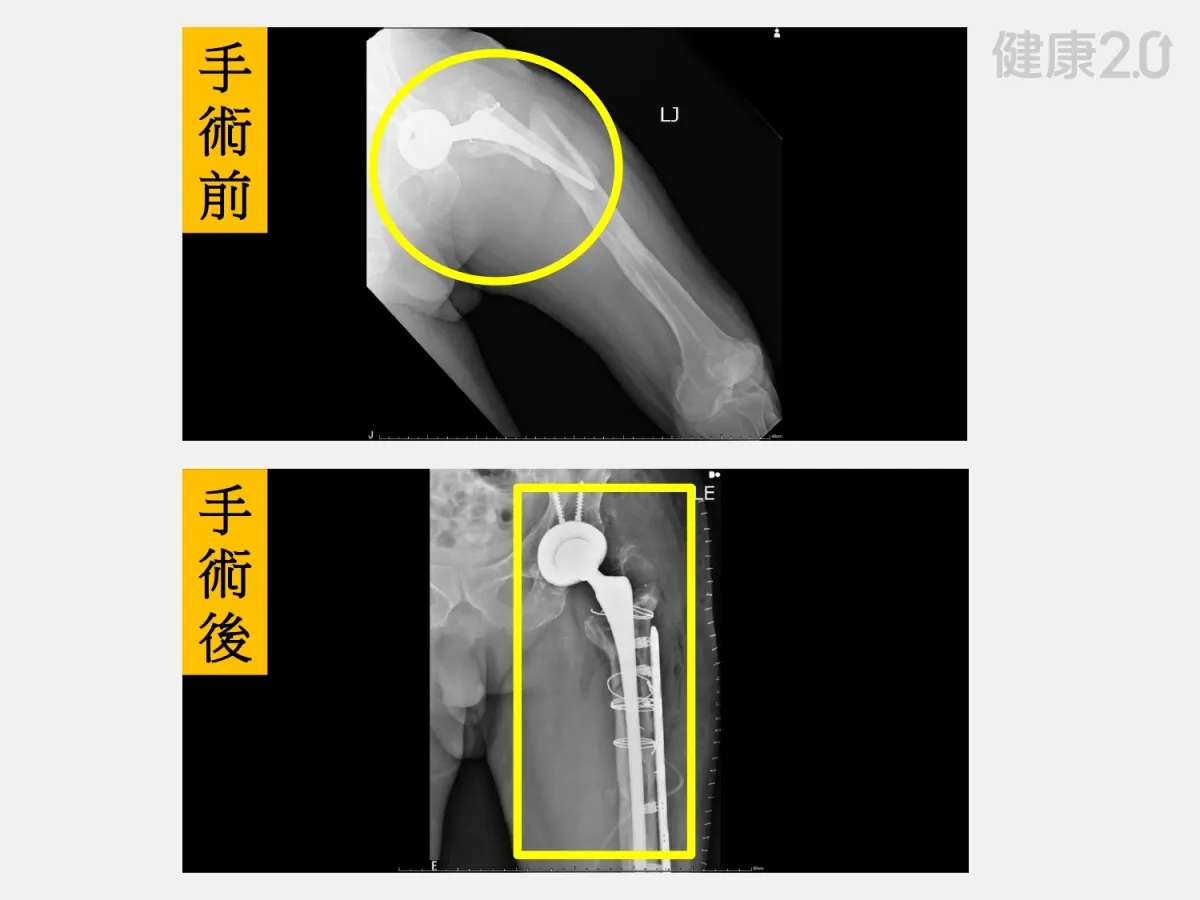

82歲的劉先生,兩側髖關節都置換過人工關節了,本以為換過人工關節就很穩固了,沒想到前不久的中秋節與家人烤肉時,不小心滑了一跤,竟造成人工髖關節旁的股骨粉碎性骨折,連原本的人工關節都鬆動了,站都站不起來!

像劉先生的案例正是長期忽視骨質疏鬆的警示。僅是簡單的滑倒,卻導致粉碎性骨折和人工關節鬆動。此次手術不僅要重新置換人工關節,還要固定骨折,對年事已高的劉先生而言,是一大挑戰。因此,醫院啟動了跨團隊整合治療。